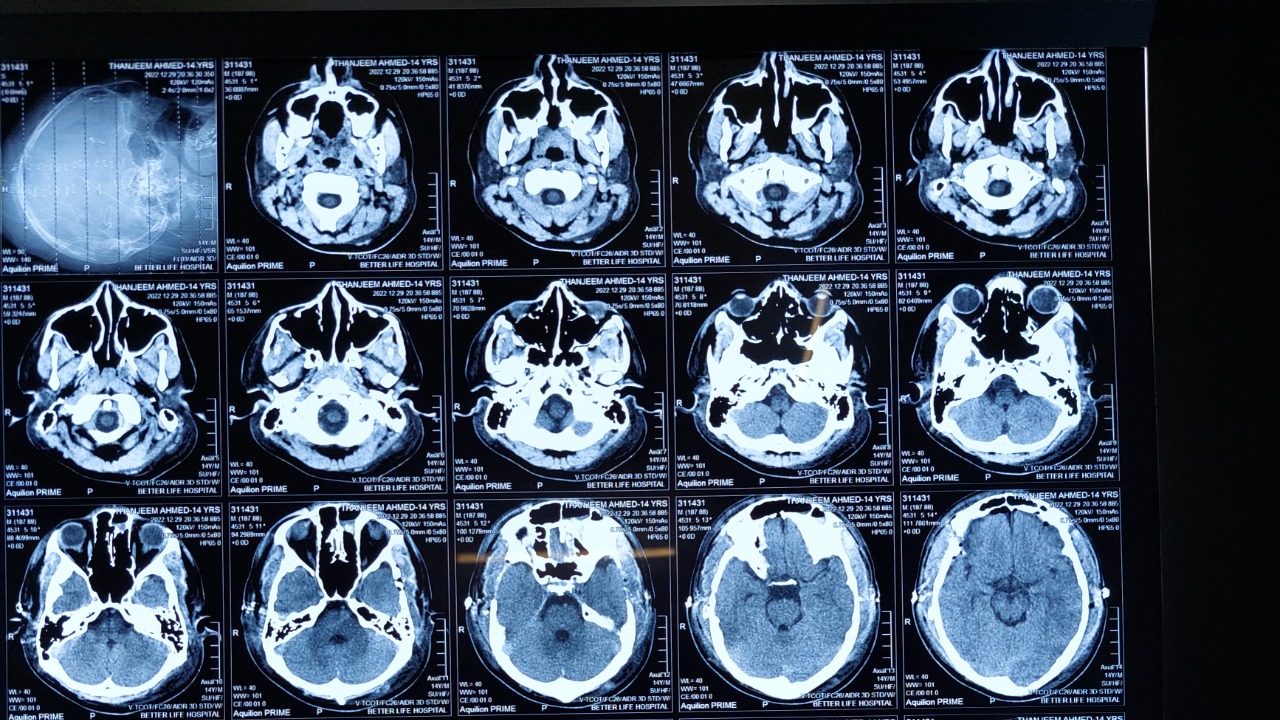

The study focused on a specific brain region that had been overlooked in previous autism research. The team discovered that abnormalities in this area could contribute significantly to autism symptoms. Their findings underscore the importance of this brain region in understanding the neurobiology of autism.

The process of reversing autism symptoms involved a series of complex scientific procedures. The researchers targeted this brain region with specialized therapies, which ultimately led to the reversal of autism symptoms in the lab models. The details of this process are captured in this SciTechDaily report.